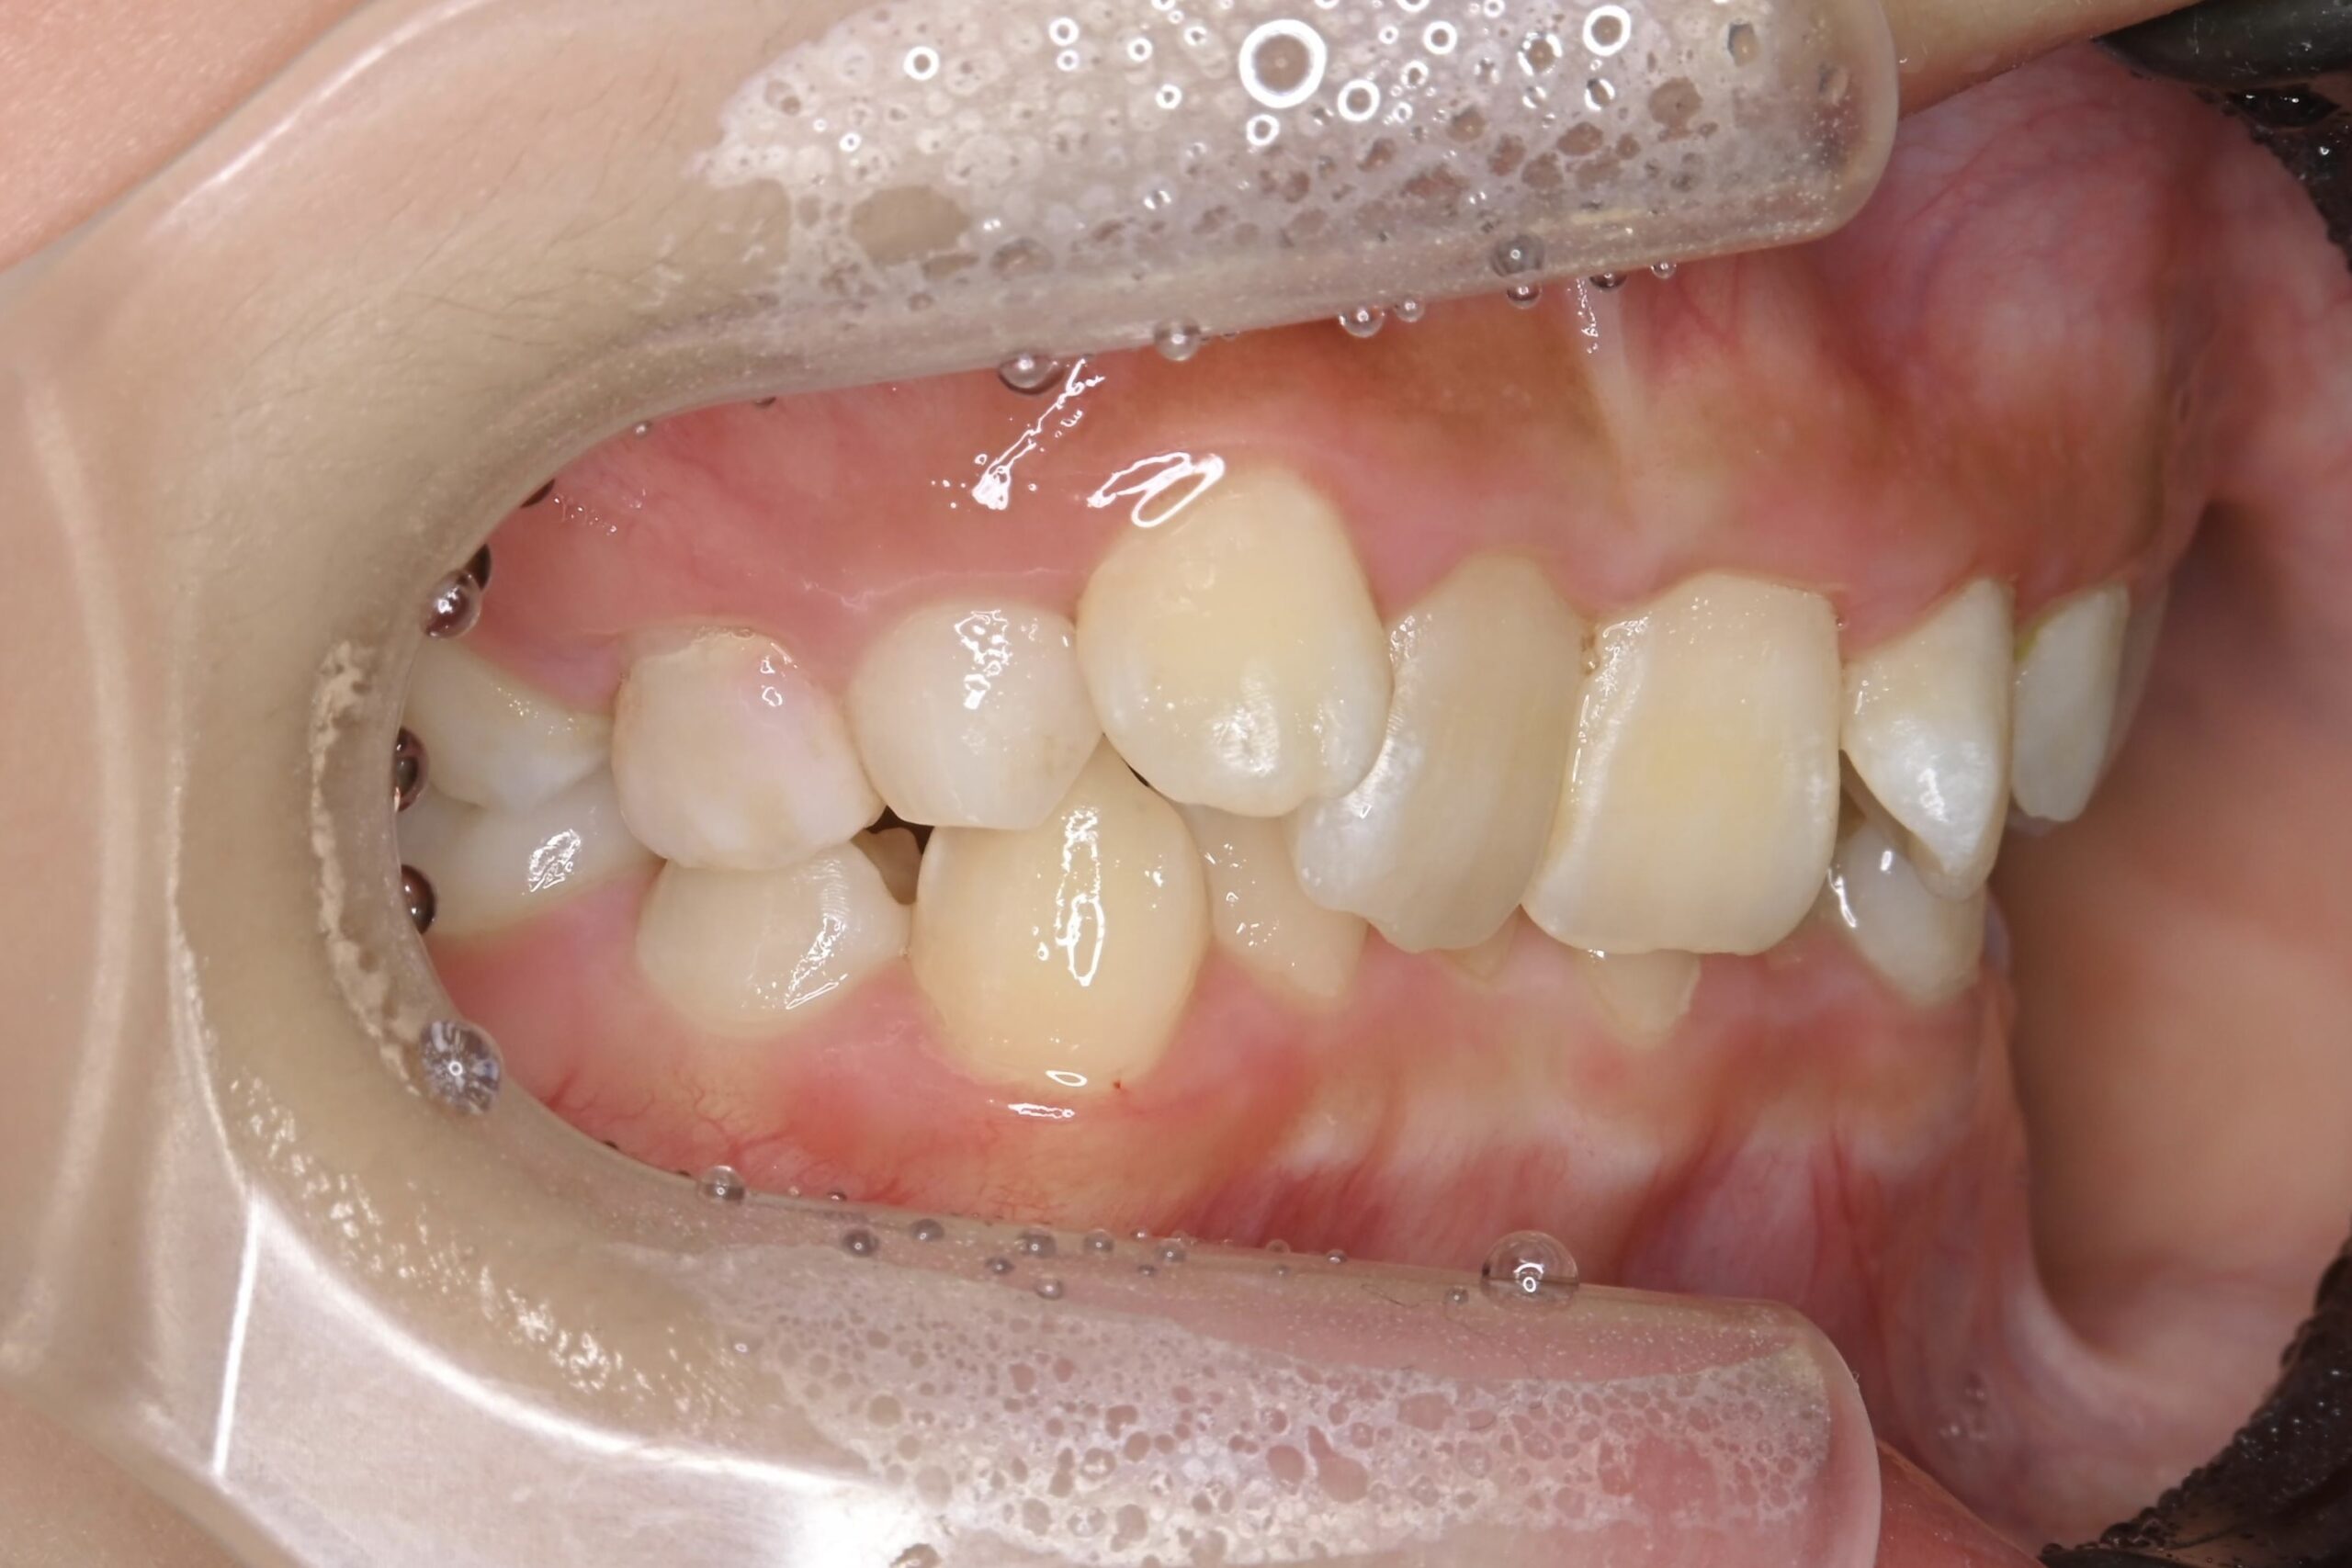

7歳 男児 小児矯正

BEFORE

AFTER

主訴 通っている歯医者で矯正した方がいいと言われて気になっている。下の前歯がでこぼこしている。

診断名・主な症状 下顎前歯の叢生を伴う過蓋咬合

治療内容 上下の歯並びの幅を拡げつつ、前歯の関係を改善しました。

使用装置 急速拡大装置

リンガルアーチ

機能的矯正装置(マイオブレース)

抜歯部位 抜歯なし

治療期間 2年 + 後戻り止め期間(3年 )

通院回数 20回

費用 50万円程度(税別)  29331

リスク・副作用 痛み、歯肉退縮、歯根吸収、抜歯に伴う出血や腫れが生じることがあります。